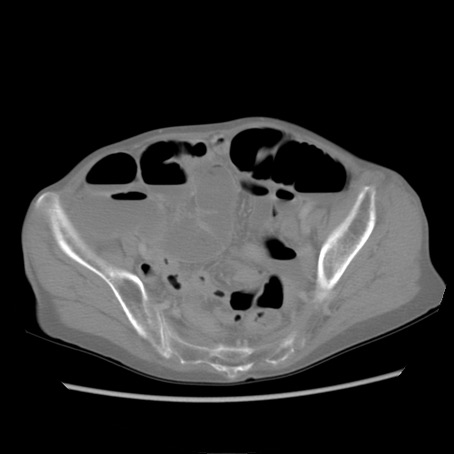

症例25(横断像)

【症例】80歳代女性

【主訴】胸のつかえ感

【現病歴】約9時間前に食後から胸のつかえた感じあり、嘔吐あり、来院。

【既往歴】胃癌(全摘)、胆摘、虫垂炎

【身体所見】心窩部に圧痛あり、反跳痛なし。

【データ】WBC 5700、CRP 0.05